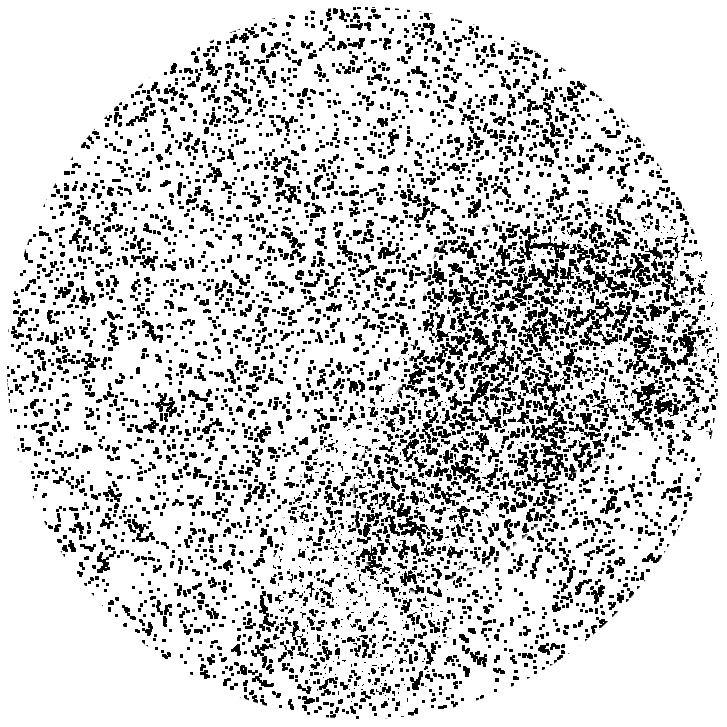

死んだ視細胞

テクスト

テクストはつぎのように見える